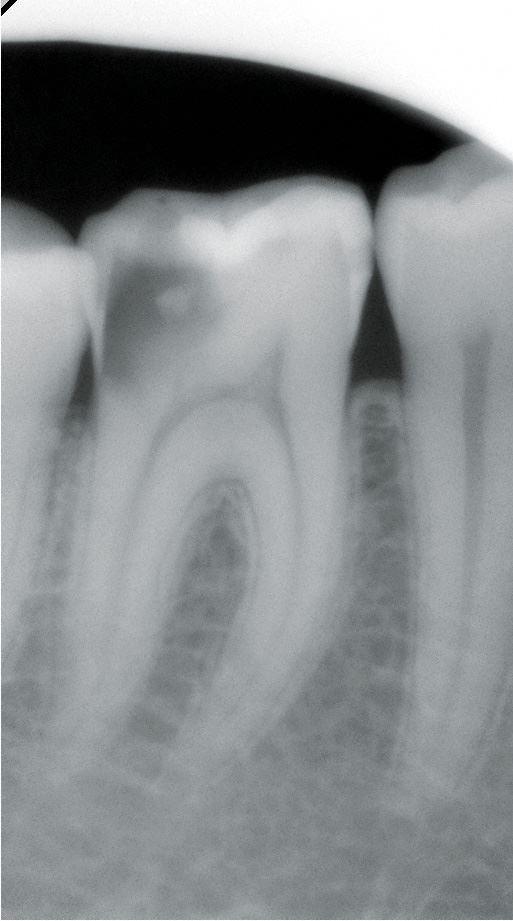

Unterschieden werden initiale Karies, Dentinkaries sowie Fissurenkaries, Approximalkaries und Wurzelkaries.

Die klinische Untersuchung, insbesondere die visuelle Inspektion (Lupenbrille) sind Standard, um auch die "hidden caries zu erkennen. Zusätzliche Maßnahmen können Röntgenaufnahmen, Einsatz von Laserfluoreszenz, Kariesdetektoren oder Fiberoptiktransillumination (FOTI) sein, um Frühstadien zu erkennen.